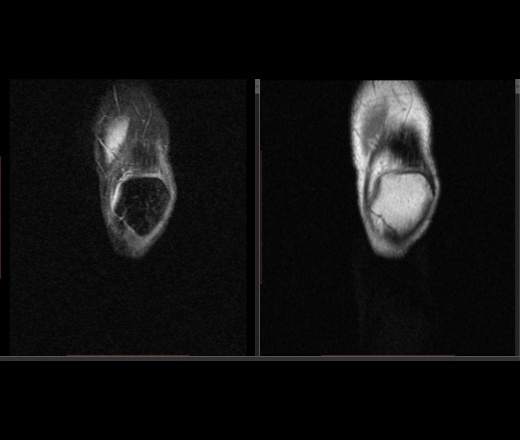

Мужчина 1963 г.р. Жалуется на боль в левом коленном суставе около 6 мес, в последний месяц стало совсем тяжко. Со слов заболел зимой, когда во время прогулки коленки сильно замерзли. Сам думаю на асептический некроз, но смущает множественность поражения.

Дмитрий, я в заболеваниях суставов не дока, но трабекулярный отек вкупе с выпотом может быть обусловлен воспалительными изменениями , но полностью начальные проявления аваскулярного некроза не могу отрицать.

я бы не поставил аваскулярный некроз. если исключена травма, дифференцировать с артритом.

Хрящ не поврежден, для артрита...